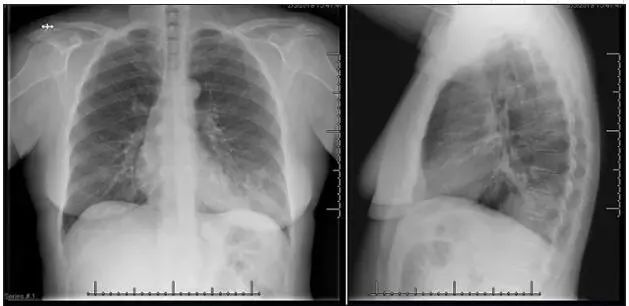

患者T 38.9℃,呼吸室内空气时SaO2为94%,WBC计数 4700 /µL。PCT 0.19 ng/mL。甲型和乙型流感的聚合酶链反应(PCR)检测结果为阴性。胸片示左肺下叶浸润(图2)。

图2